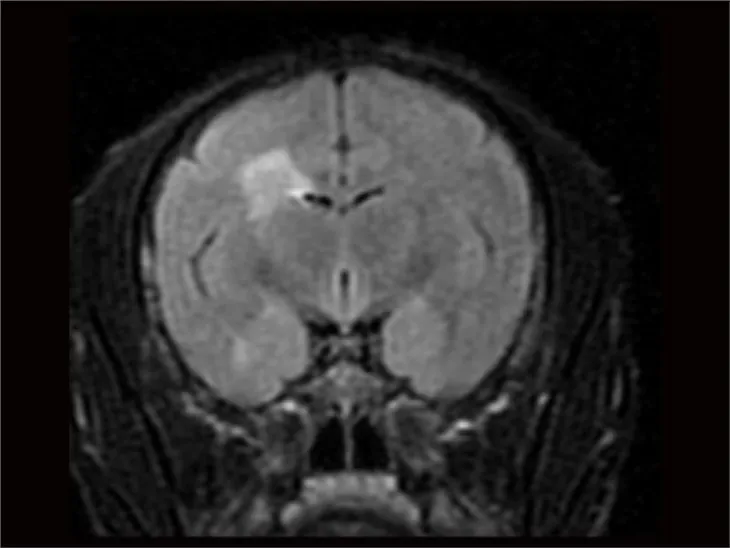

تتضمن نماذج NHP الخاصة بنا نموذج النزيف في الجسم الحي ، ونموذج تحويلة Arterio-Venous (AV) ، ونموذج ركود Wessler ، ونموذج تخثر الشرايين الناجم عن FeCl3. مدة الدراسة القياسية لهذه النماذج هي ساعات ، مع تحديد نقاط نهاية الدراسة من خلال التصميم التجريبي المحدد. تشمل نقاط النهاية السريرية وقت النزيف / الوزن ، ووزن الجلطة / الجلطة ، واختبارات التخثر ، وسرعة تدفق الدم ، وتصوير التخثر.

تم تصميم نماذجنا لتوفير تقييمات شاملة للإرقاء ، وتقييمات السلامة ، ودراسات مضادة للتخثر ، ودراسات عوامل التخثر ، وتقييمات التخثر داخل الحجاج. تمكننا هذه النماذج من اكتساب فهم أعمق للآليات الأساسية للتخثر والتخثر ، وتوفر أداة قوية لتطوير واختبار علاجات جديدة لأمراض الأوعية الدموية.